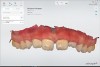

Fig 6. Digital model showing teeth to be extracted.

Figure 6